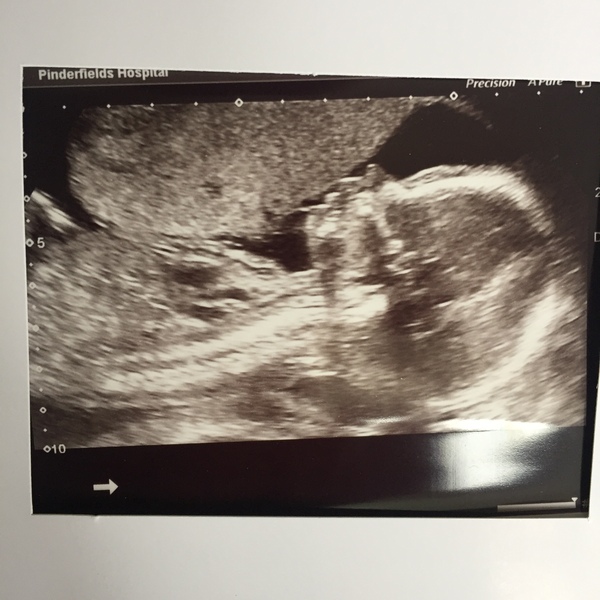

I do the same, OH just laughs at me and takes the mick for a while haha. good luck with your scan too! my lil girl is normally very active in a morning, but when I had my scan, think she was having a snooze, the person who scanned me had to nudge her with the probe so he could get all her measurement's, she must be hard work like me

Thank you @RomPom and its always emotional hearing the heartbeat isnt it?

Glad your scan went well @Gemsie1984 got fingers crossed too for your results